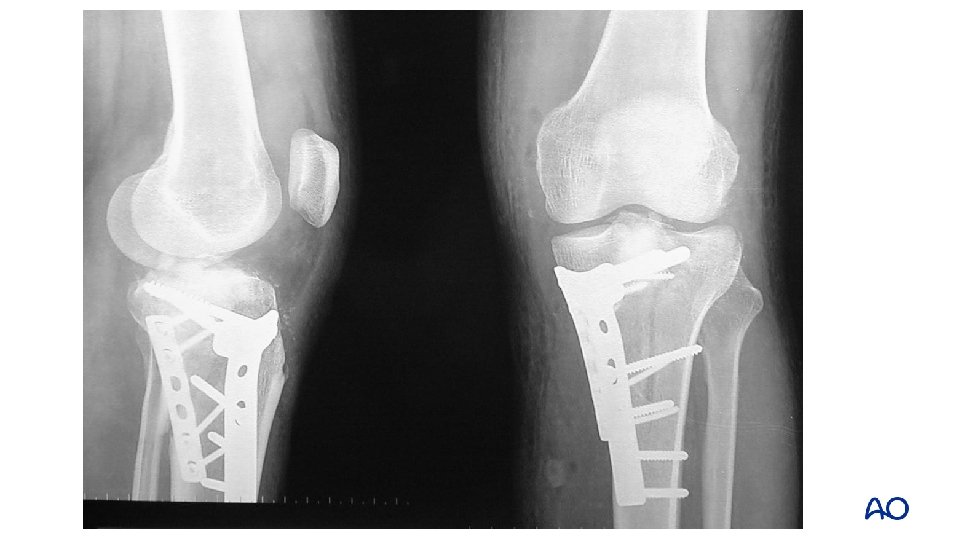

Schatzker type IV: 2 -column fracture—flexion varus Varus flexion mechanism medial posterior

Approach: midline and posteromedial

Midline approach Fracture window Posteromedial approach

1 -year follow up